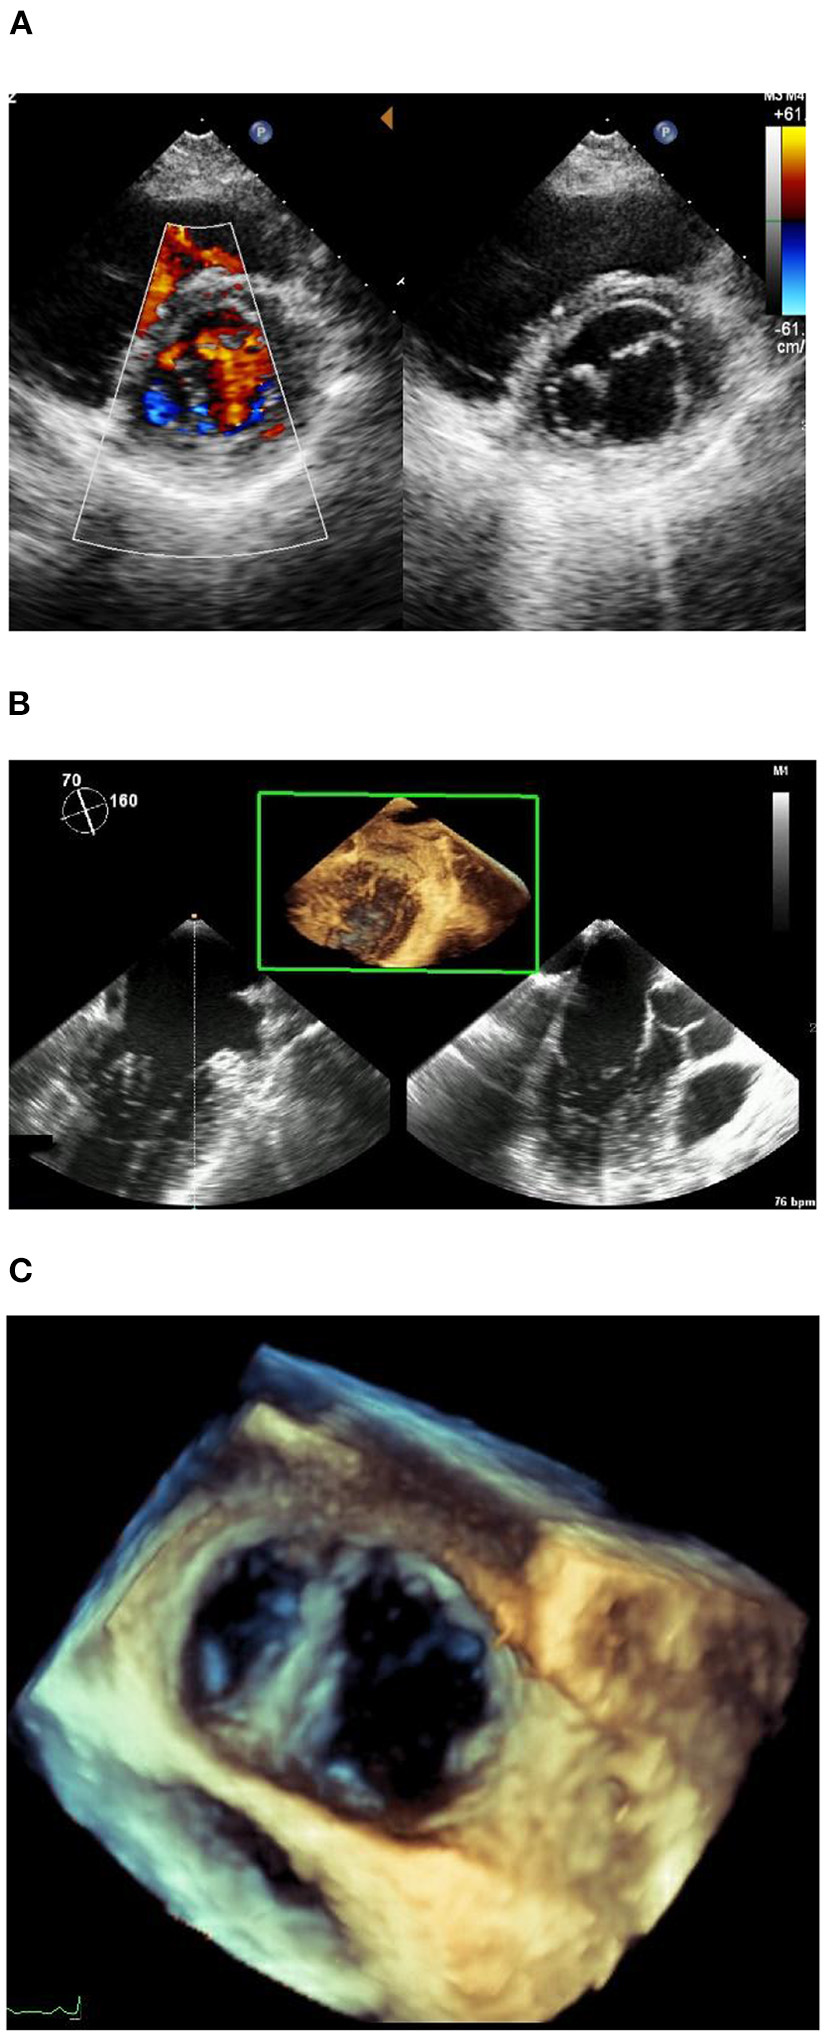

A 38-year-old asymptomatic woman with a previous history of subclinical hypothyroidism and long-term use of sodium thyroxine presented to the outpatient clinic with “abnormal ECG for 1 year.” No heart murmur was detected. The short axis view showed two oval-shaped orifices, one large and one small, aligned left and right, with the small hole tendon not visible (Figure 1A). Color Doppler examination showed two bundles of blood flow across the orifice. There was no mitral stenosis (MS) and trivial mitral regurgitation (MR) (peak mitral E wave velocity = 97.2 cm/s, peak gradient = 4 mm Hg, peak mitral A wave velocity = 47.4 cm/s, peak gradient = 1 mm Hg). The remaining valvular structures were not significantly abnormal, and the tricuspid valve had mild regurgitation. The left ventricular ejection fraction and diastolic function were normal. In addition, no other cardiac structural abnormalities were detected. The transesophageal echocardiogram (Figures 1B, C) was consistent with the transthoracic echocardiogram, and the diagnosis of congenital heart disease was confirmed as DOMV. Additional movies are available in the Supplementary material.

(A) Short axis of echocardiogram image. (B) Transesophageal echocardiogram. (C) Transesophageal echocardiogram.